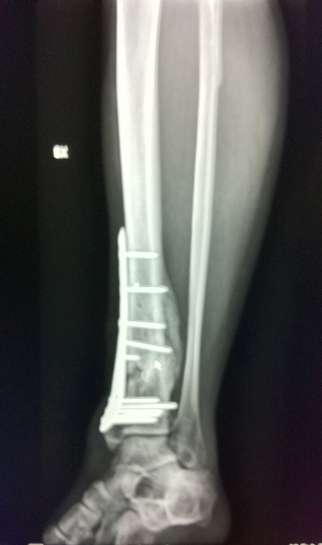

Seconda operazione: rimozione placca rotta e "montaggio" nuova placca:

Nuova placca

[​IMG]

[​IMG][​IMG]

La prima operazione è stata nel 04/2010 (prima piastra)

La seconda nel 10/2010 (sostituzione piastra)

La terza nel 04/2012 (rimozione seconda piastra)